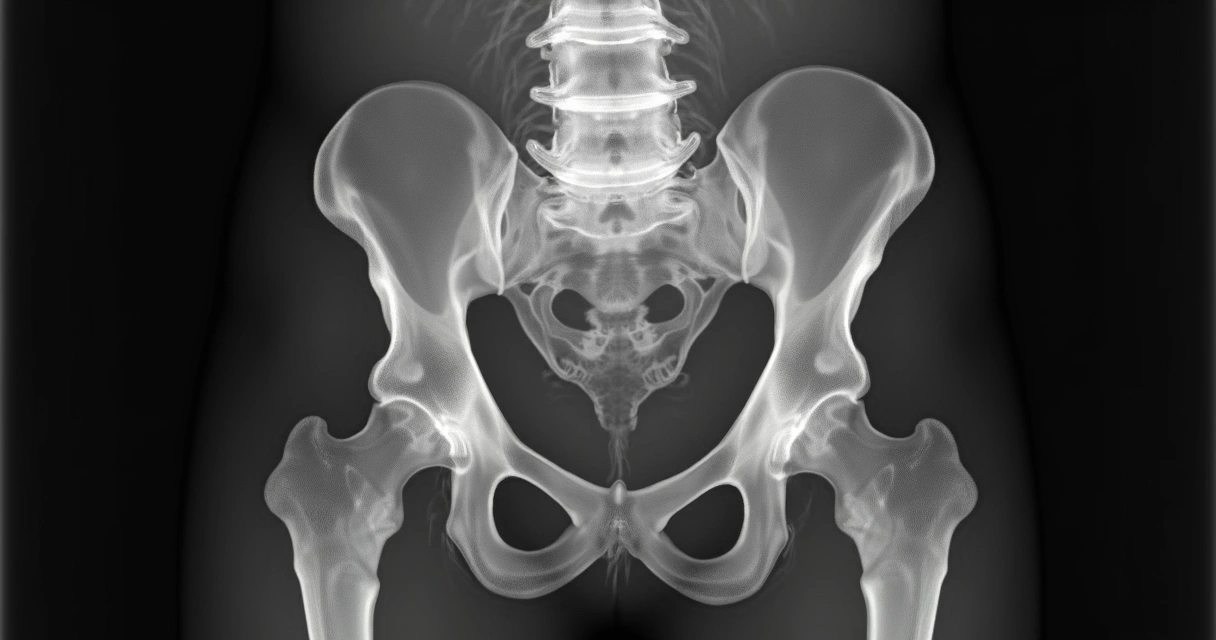

O primeiro passo é uma avaliação clínica detalhada. Durante a consulta, avalio histórico, sintomas, limitações e realizo manobras específicas. Os exames de imagem são fundamentais para confirmar o diagnóstico e excluir outras causas de dor no quadril. Entre eles, destaco:

- Radiografia do quadril: mostra o grau de desgaste, presença de osteófitos (bico de papagaio) e estreitamento articular.

- Ressonância magnética: indicada em casos iniciais ou duvidosos, ajuda a avaliar cartilagem, ligamentos e identificação precoce de osteonecrose (osteonecrose pode envolver morte do tecido ósseo nessa região do quadril).